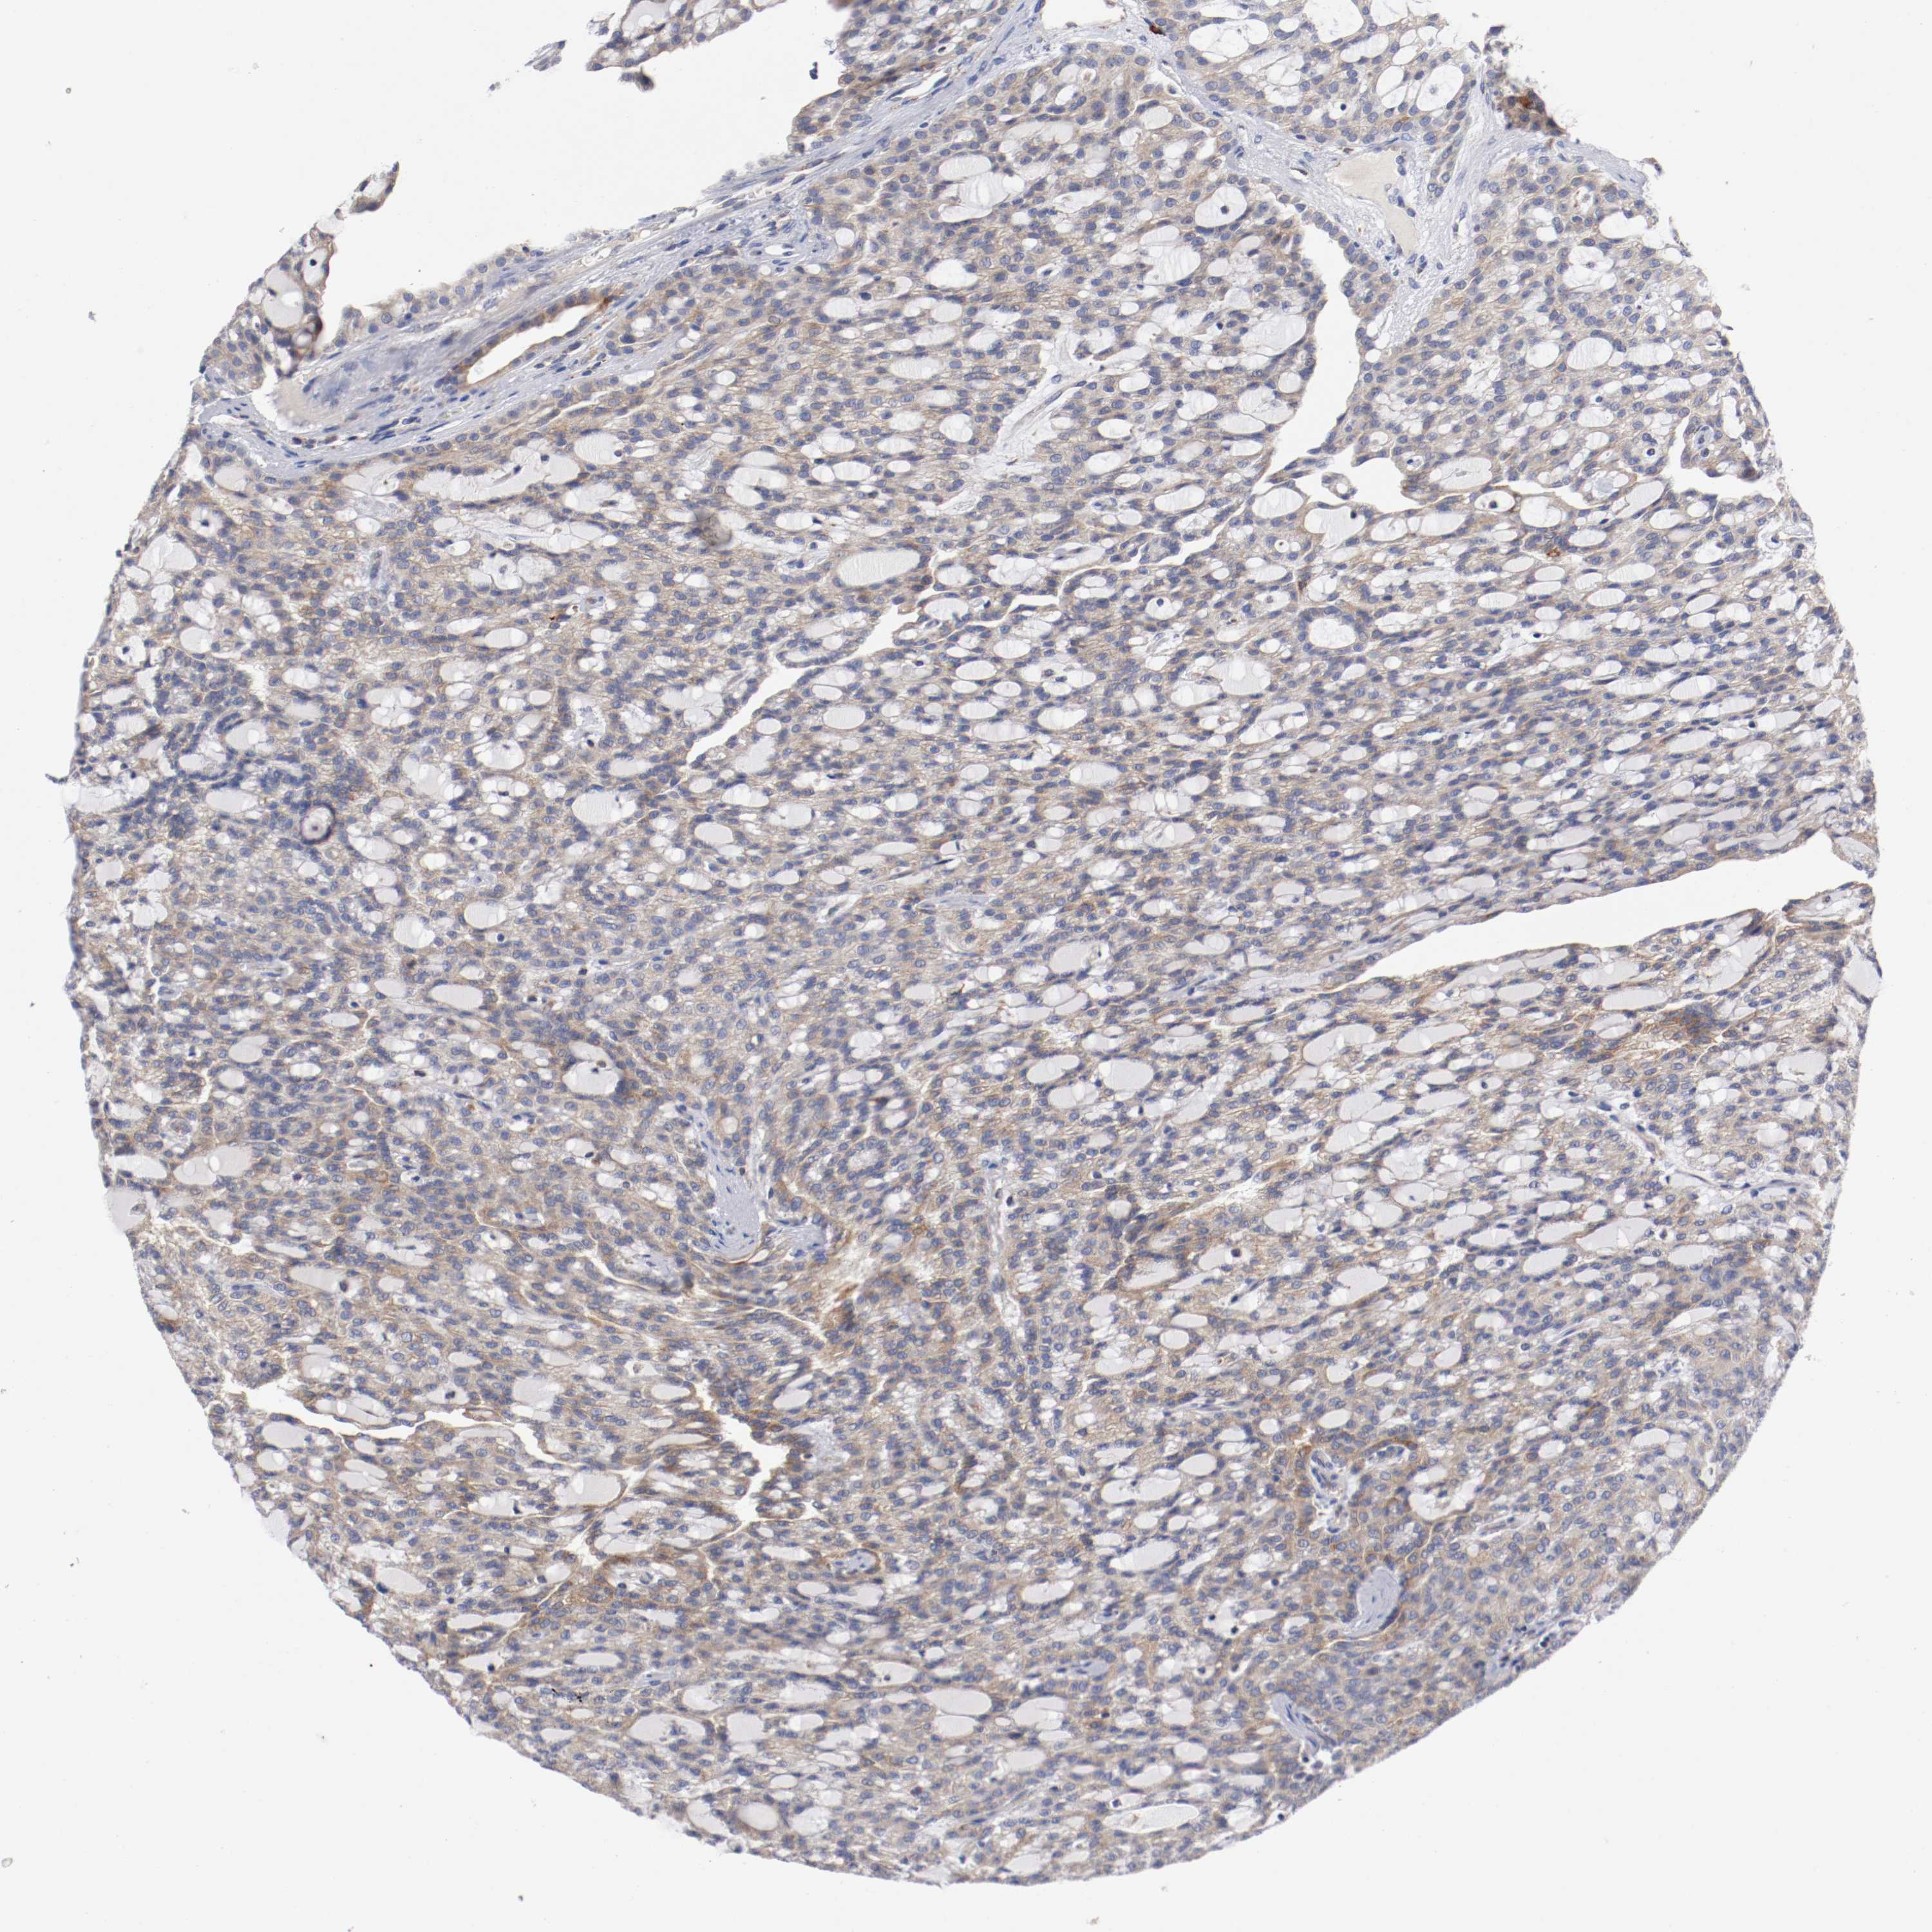

CANCER RENAL CANCER Show tissue menu

KICH TCGA KIRC TCGA KIRC VALIDATION KIRP TCGA PROTEIN RCC CPTAC PROTEIN EXPRESSION